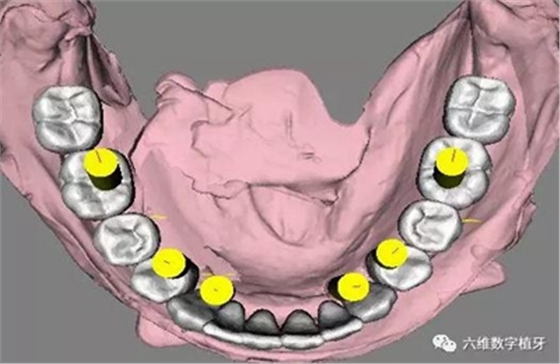

1. 選擇適當(dāng)?shù)姆N植體尺寸,精確的避開前牙區(qū)骨壁較薄的地方。

2. 預(yù)先在軟件里面進(jìn)行排牙,根據(jù)最終修復(fù)的效果精確放置種植體的位置。

3. 充分評(píng)估患者的骨質(zhì)條件,手術(shù)之前事先將固定的臨時(shí)義齒做好,進(jìn)行即刻負(fù)重。